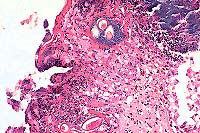

Case 1: Liver. Note focus of coagulative necrosis, mild infiltration of lymphocytes and plasma cells, and scattered hepatocytes containing eosinophilic intranuclear inclusions.(40x obj)

Case 1: Esophagus. Necrotic mucosa and submucosal glands layered with basophilic bacteria, multifocal clusters of bipolar plugged nematode eggs. (20x obj)

Case 1: Small Intestine. Demonstrates focal hemorrhage expanding lamina propria with sloughing & necrosis of mucosal epithelium.(4x obj).

The lesions are consistent with duck viral enteritis, a herpes virus infection. This submission includes tissues from two different birds. The liver on most slides has discrete areas of necrosis and numerous intranuclear eosinophilic inclusions in hepatocytes that are not necrotic. The liver on some slides has diffuse congestion with areas of hemorrhage, necrosis and fibrin with abundant bacteria and no inclusions. The esophagus in most slides has complete ulceration with occasional inclusions in the glandular epithelium. On a few slides some mucosa is left which contains eosinophilic cytoplasmic inclusions that may be pox virus. A few slides also have Capillaria in the necrotic mucosa.

Histologic lesions include gastrointestinal necrosis, hepatocellular necrosis, necrosis and loss of lymphoid tissue, and necrotizing vasculitis. As in this case, eosinophilic intranuclear viral inclusion bodies are present in hepatocytes, biliary epithelium, gastrointestinal epithelium, and lymphoreticular cells associated with these necrotizing lesions. Intranuclear inclusions have also been reported in vascular endothelium. As the contributor observed, some of the esophageal epithelial cells contain eosinophilic intracytoplasmic inclusion bodies. While these inclusions may be poxviral inclusions, conference participants noted that intracytoplasmic herpesviral inclusions have been reported in a natural outbreak of DVE in muscovy ducks.2